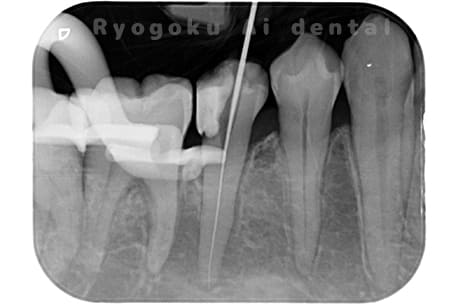

根管内の異物

- 原因

- 根管内異物(ファイル破折)による慢性根尖性歯周炎

- 治療期間

- 3ヶ月

- 治療内容

- マイクロスコープを使用した根管内異物除去並びにマイクロエンド

- 治療費用

- 121,000円(ファイル除去費用も込み)

他院で細い器具(ファイル)が根管内に破折した状態で、咬合痛を主訴に来院された患者様です。ファイルをマイクロスコープ下で除去し、根管治療を行ないました。